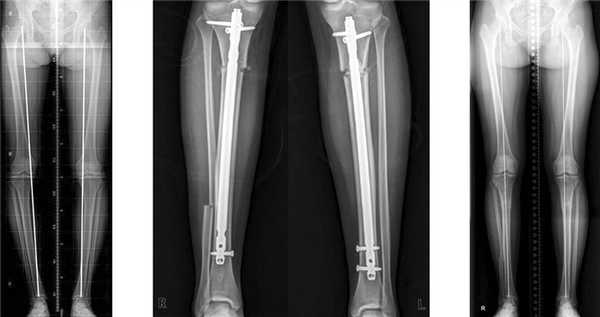

Эта методика получила наименьшее распространение по сравнению с двумя другими (пластинами и аппаратами). Несомненным достоинством является стабильная фиксация, что позволяет оперировать сразу обе конечности и обеспечивает раннюю функцию и опороспосбность. Суть методики заключается в том, что после предварительного рассверливания костномозгового канала бедренной или большеберцовой кости в него вставляется штифт соответствующего диаметра.

Схема введения, положение штифта внутри кости и рентгенограммы после операции

Несмотря на то, что штифты вводятся через небольшой разрез, нельзя считать эту методику малотравматичной. Существует риск развития серьезных осложнений. Если, допустим, при использовании аппарата Илизарова воспаление или нагноение носит локальный, поверхностный характер и легко излечивается, то при интрамедуллярном остеосинтезе нагноение грозит распространением процесса по всему костномозговому каналу. Также очень сложно добиться симметричной коррекции обеих ног, что имеет важное значение в косметической хирургии.

Учитывая риск развития серьезных осложнений, не хотелось бы рекомендовать эту методику при эстетической коррекции формы ног. Имеется целесообразность применения штифтов при удлинении, когда длительные сроки фиксации аппаратом Илизарова значительно снижают качество жизни пациентов.